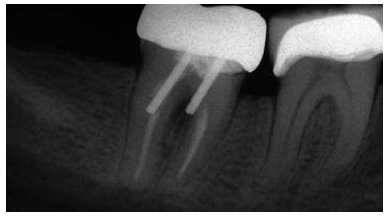

圖4:下頜第二前磨牙的根尖片,經(jīng)由螺紋樁進(jìn)行修復(fù),導(dǎo)致根折

5:下頜第二磨牙牙根穿孔的根尖片,樁道預(yù)備的器械未與根管壁相平行

研究結(jié)果表明牙根折斷是樁核修復(fù)失敗的第二個(gè)最為常見(jiàn)的原因。多個(gè)原因已經(jīng)被證實(shí)與牙根折斷潛在相關(guān),其中包括大直徑的樁修復(fù),短樁和帶螺紋的樁(圖 4)。臨床上推薦樁的直徑不能超過(guò)牙根直徑的1/3,并且樁直徑應(yīng)當(dāng)與牙根的平均尺寸成比例地相關(guān)。

對(duì)于牙體解剖、牙根結(jié)構(gòu)、形態(tài)及其變異的良好理解,同時(shí)使用恰當(dāng)?shù)念A(yù)備方向,能夠幫助牙醫(yī)在樁道預(yù)備過(guò)程中避免出現(xiàn)過(guò)多的切削牙體組織和牙根穿孔。預(yù)備樁道時(shí),器械的方向必須與根管的方向相平行(圖 5)。